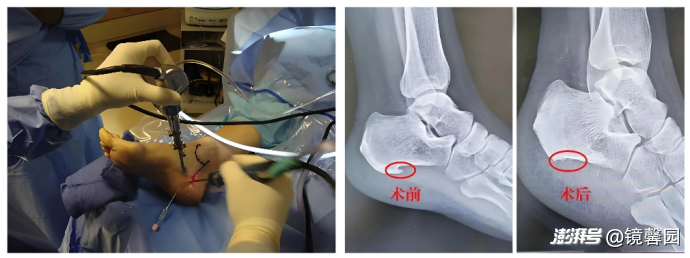

手术方法:微创关节镜手术

功效:磨去骨刺,清除脚底炎症,减少足底筋膜的压力

优点:减轻足跟疼痛,疗效肯定;术后结合康复治疗,继续巩固结果。